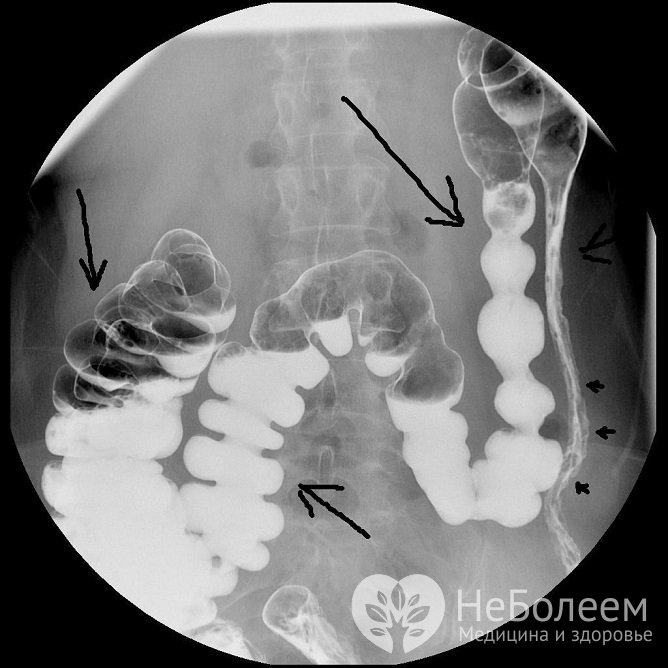

• при проведении рентгенологического исследования с контрастным веществом отмечается сглаживание структуры слизистой оболочки, исчезновение гаустр (симптом «водопроводной трубы»).

Хронический колит, результаты ирригоскопии Хронический колит: результаты ирригоскопии